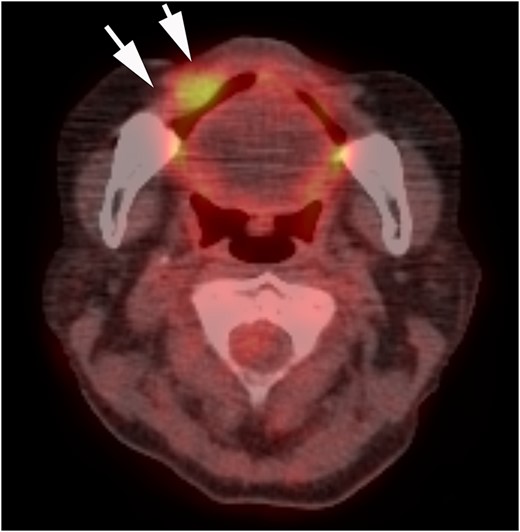

A 62-year-old woman had a rough-surfaced tumor measuring 25 × 10 mm2 overlying the region from the mucosal surface of the right labial commissure to the lower lip (vermilion border) (Fig. 2). Positron emission tomography-computed tomography was used to detect the local invasion in the buccal mucosa (Fig. 3). A preoperative biopsy was performed, and the tumor was diagnosed as malignant (carcinoma in situ).

PET-CT findings. Invasion localized to the right buccal mucosa is visible (arrow).